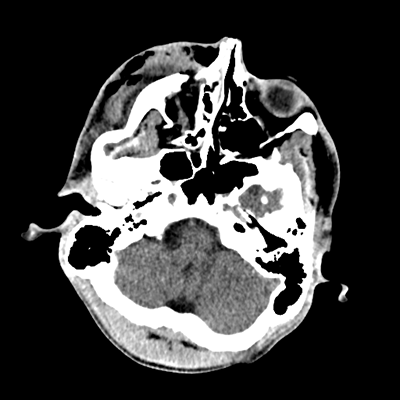

Initial vitals are notable for BP 111/67, HR 119, SpO2 100%, T 37.8C. She undergoes a whole-body CT scan. Trauma surgery also evaluates her. She has a zygomaticomaxillary complex fracture, comminuted fracture of her humerus, and fractures of ribs 2-6. Her non-contrast head CT is shown below. Plastic surgery evaluates her and recommends non-emergent operative repair of her facial fracture.

The patient has sustained multicompartmental hemorrhages—small amounts in the parenchymal, subarachnoid (mainly right frontal), subdural (right frontal, anterior temporal in particular), and intraventricular (layering in the right occipital horn) spaces. It’s a more subtle finding, but you can also see that the right hemispheric convexity has less sulcation, suggestive of cerebral edema on that side. There’s the right frontal contusion with hemorrhage there. There are also two small IPHs, in the right thalamus and left internal capsule. What do these represent? Likely diffuse axonal injury (DAI).